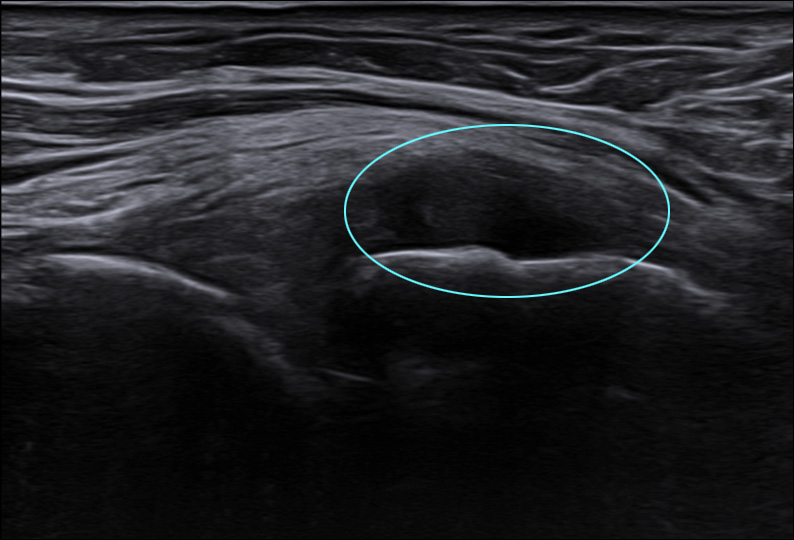

무릎을 구부릴 때, 펼 때 통증이 심하고

부종도 크던 50대 환자.

초음파 검사시 염증 소견, 엑스레이에서 관절염 진행 상태로,

하이펑쳐 시술과 침 치료로 호전